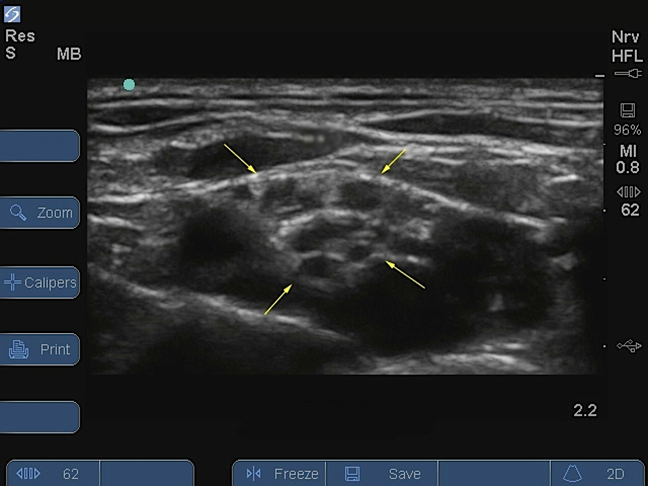

Bild: M-Turbo, Plexus brachialis, supraklavikulare Ebene -2, nach der Injektion

Plexus brachialis, supraklavikularer Zugang

Gelbe Pfeile: Nerv